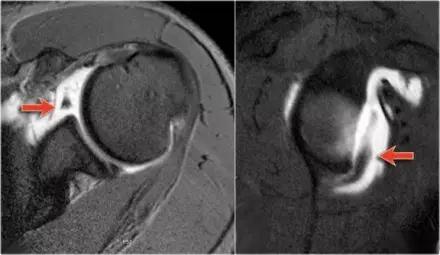

骨性 Bankart 损伤的 MR(左)和 CT(右)(来源:ShoulderDoc)

骨性 Bankart 损伤的 MR(左)和关节镜图(右)(来源:ShoulderDoc)